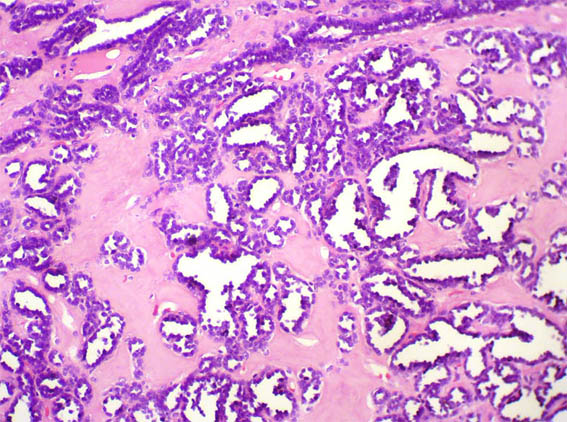

Figura 3.

H&E, X200.